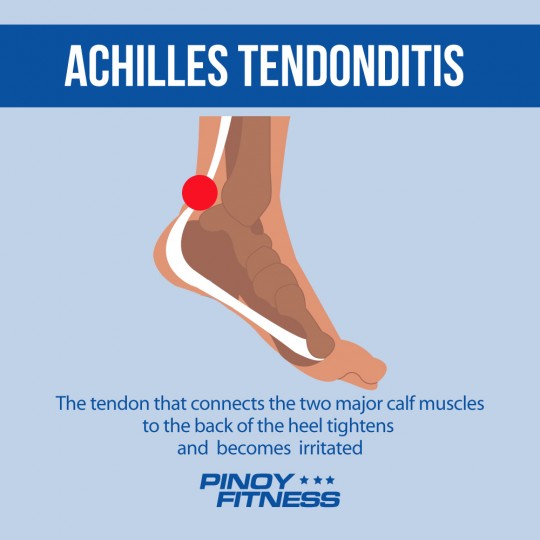

7 Common Running Injuries and What You Can Do About Them | Pinoy Fitness